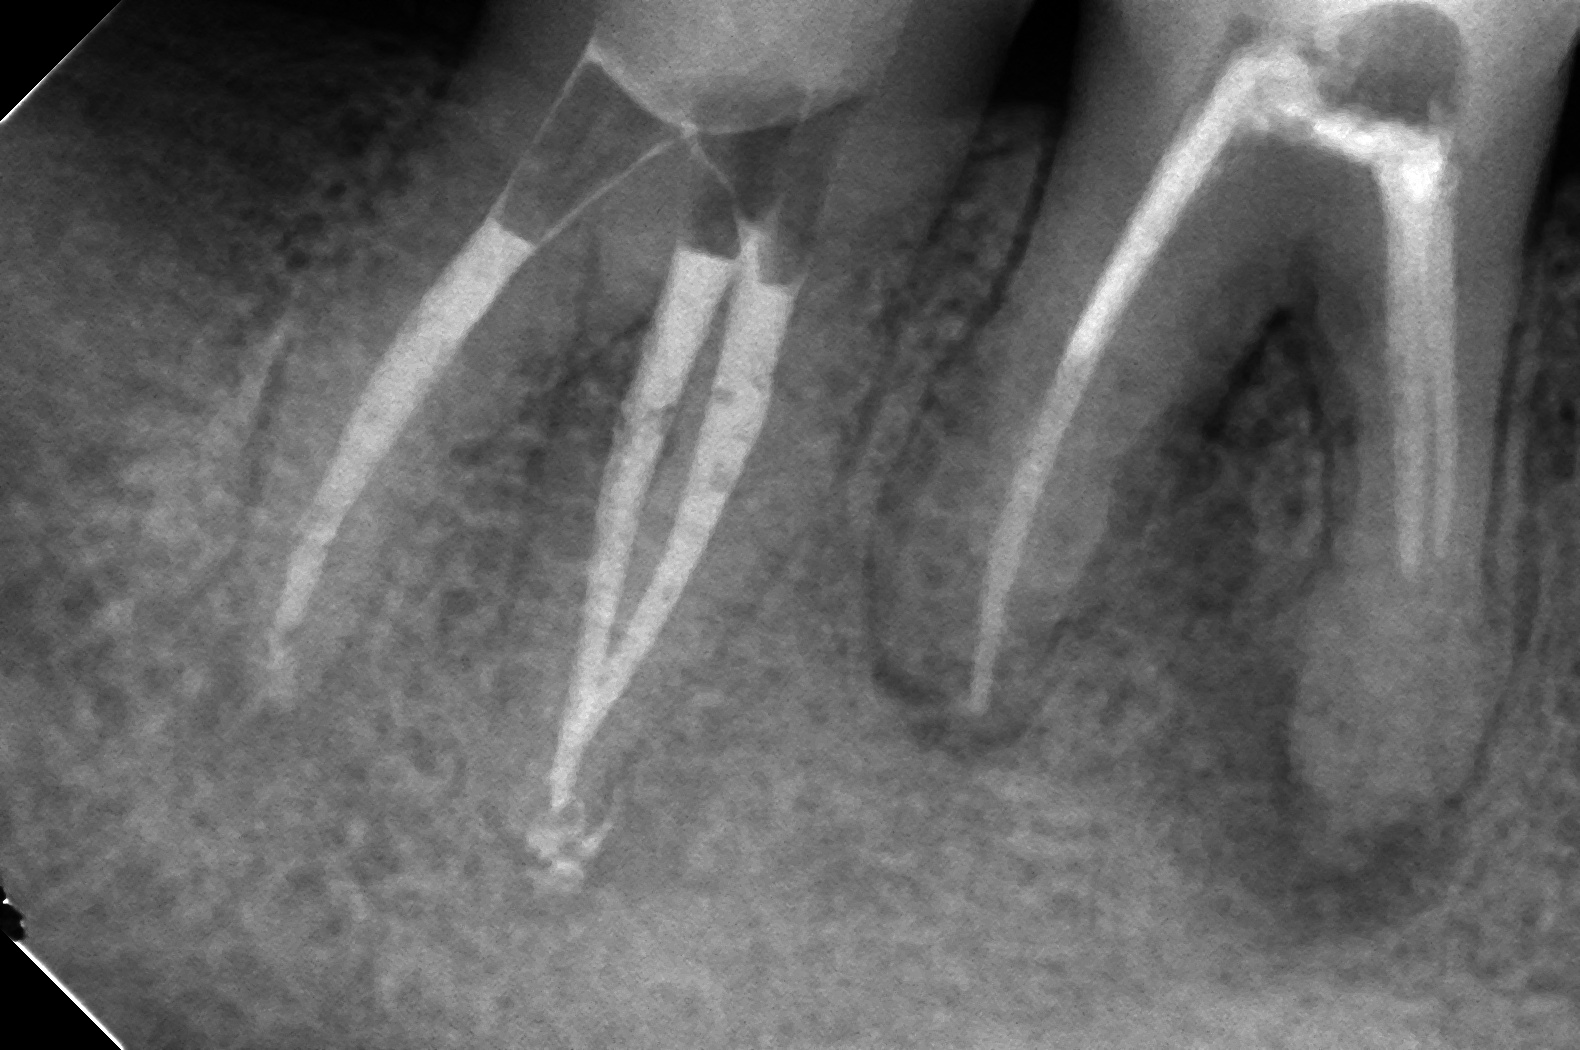

7番の痛みがどうしても引かないから診て欲しいとの依頼を受け、診させていただいた症例です。

自発痛が強く、仮蓋が外してありました。

湾曲部あたりから、切削感がバージンな感じだったので、根尖まで綺麗にお掃除し、その日は終了。

先端で癒合してるんですね。

シーラー出ちゃったけど治ってよかったです。